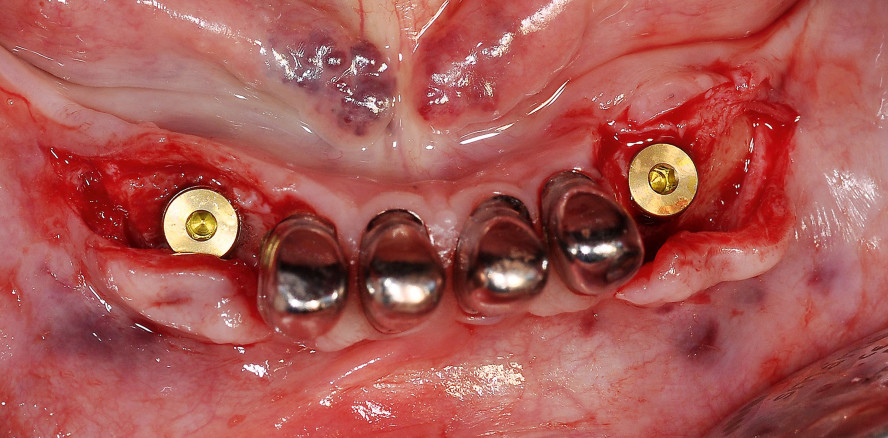

Es erfolgte eine Panoramaschichtaufnahme mit zwei Röntgenreferenzkörpern und eine klinische Untersuchung (Abb. 1 und 2). Acht Wochen nach dem Verlust der unteren Zähne 43 und 33 erfolgte die Insertion von zwei 3,8 mm breiten und 11 mm langen Implantaten (CAMLOG Vertriebs GmbH) in die teilweise regenerierten Extraktionsalveolen (Abb. 3–7).

Die Freilegung erfolgte neun Wochen nach Implantatinsertion mit zwei kleinen apikalen Verschiebelappen in Form von Spaltlappen und leicht lingualer Schnittführung. Es wurden zwei 4 mm bottleneck-Gingivaformer (CAMLOG Vertriebs GmbH) in die Implantate eingeschraubt und die präparierten Lappen adaptiert (Abb. 17).

Die Arbeit wurde zehn Tage nach Abformung eingesetzt. Die Gingivaformer wurden gegen die Titanabutments getauscht, welche mit 25 Ncm angezogen wurden (Abb. 22). Die Schraubenkanäle wurden mit Guttapercha verschlossen und die Primärteleskope mit Harvard zementiert (Abb. 23). Eine Röntgenkontrolle erfolgte, um sowohl etwaige Zementreste als auch den Sitz der Primärteleskope auf den Abutments zu kontrollieren.